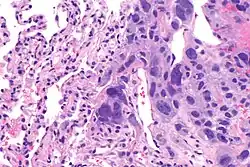

Choriocarcinoma

Choriocarcinomas are exceptionally rare which account for 2.1%-3.4% of all OGCTs.[10] Under gross examination, the syncytiotrophoblast cells are aligned in a plexiform arrangement with the mononucleated cytotrophoblast cells surrounding the foci of the hemorrhage.[1] Choriocarcinomas can be divided into gestational choriocarcinomas and non-gestational choriocarcinomas which have immunohistochemical differences.[11]